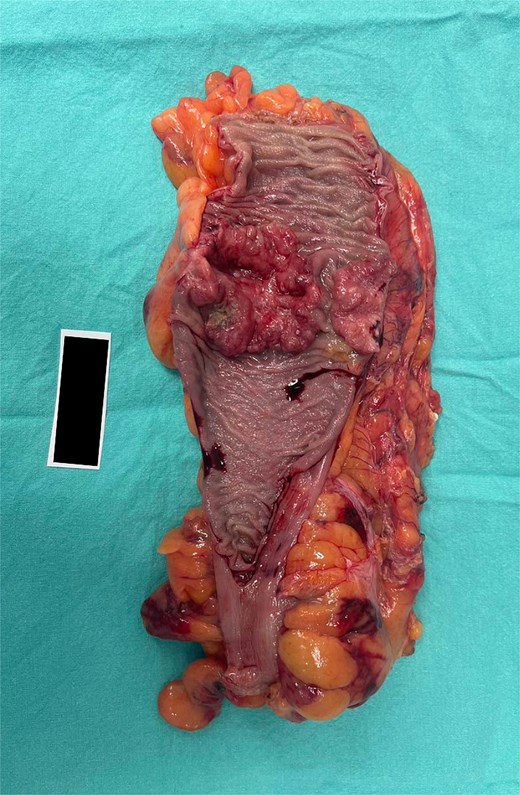

A kidney mass was found at the lower pole of the right kidney without invasion of Gerota’s fascia. A 100% circumferential fungating mass was found in the sigmoid colon without serosal invasion (Fig. 4).

Surgical specimen of case 1 showing synchronous tumors: Sigmoid colon cancer on the right and RCC on the left.